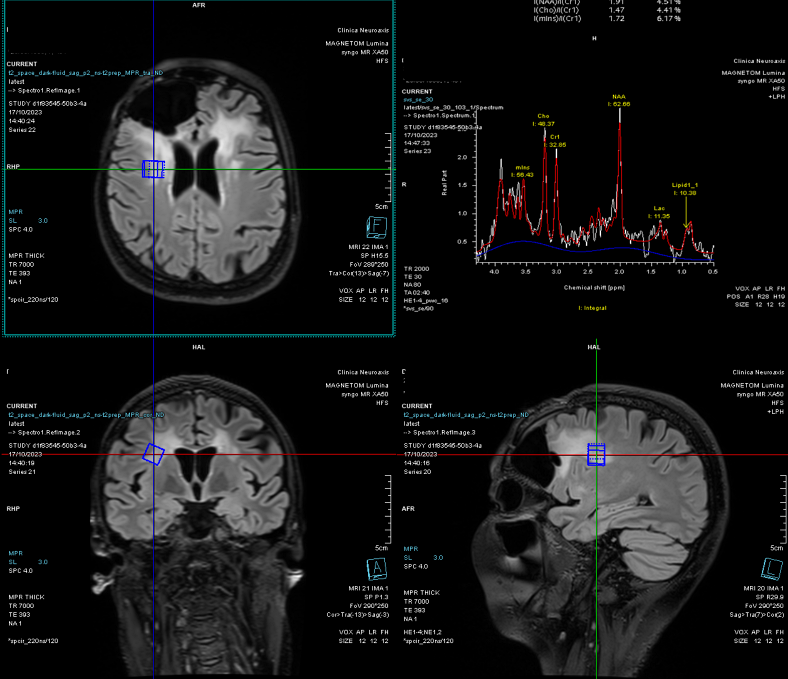

Spectroscopia RMN a confirmat o progresie tumorală de tip low-grade, cu peak de colină (Cho) și N-acetil-aspartat (NAA).